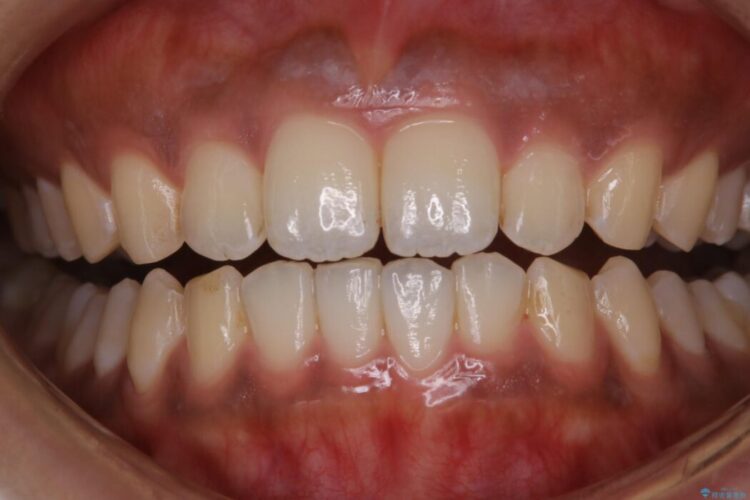

PMTCでは、専門の機材を使用し、歯の表面の凸凹にミネラルを補給して、ツルツルの表面に仕上げます。定期的にPMTCを行うことにより、歯質の強化になり着色がつきにくい状態になります。